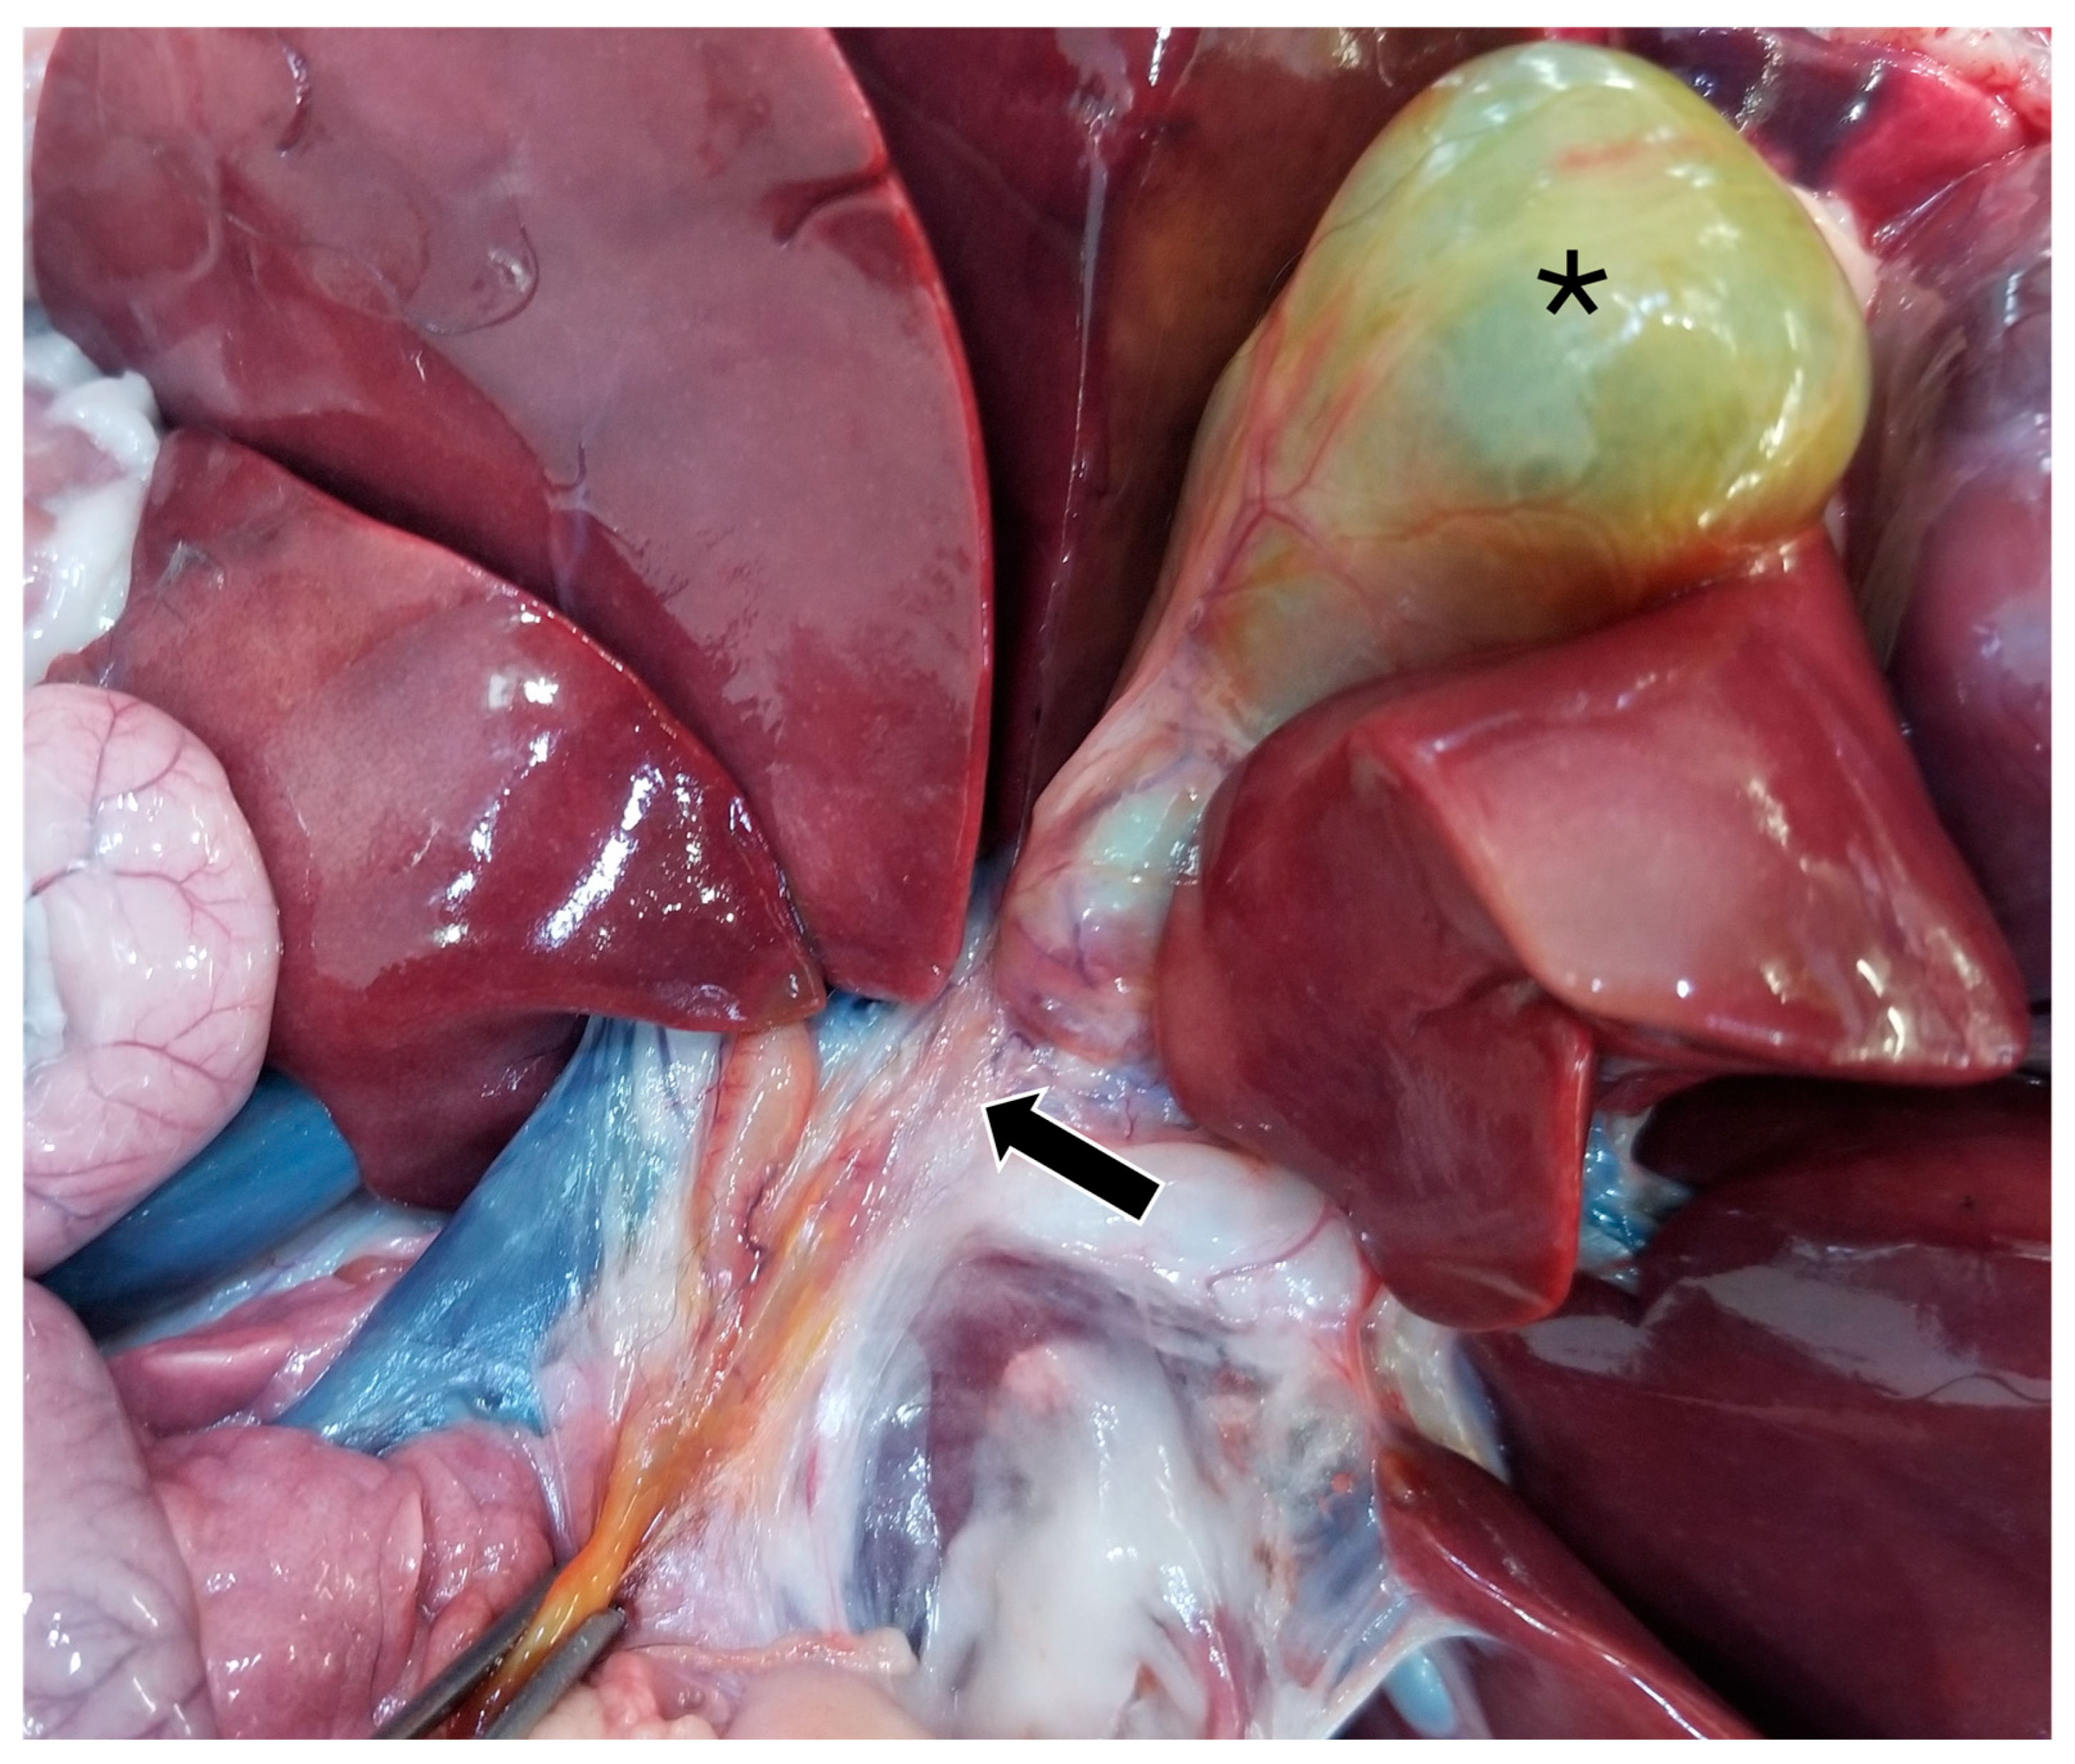

On gross pathology, the animal was markedly small compared to what would be expected for the reported age of the animal. The liver weighed 0.38 kg (3.8% of body weight). There were numerous, multifocal to coalescing, pinpoint, pale tan foci scattered throughout all liver lobes. The bile duct was patent. The gallbladder was distended with bile and just proximal to where the cystic bile duct joins the common bile duct (Figure 5), there was a 1-cm-long abrupt narrowing of the duct with a luminal diameter of 2 mm (stenosis). The wall of the duct in the region of stenosis was thickened up to 1 mm. A 7.5 × 2.5 × 1 cm portion of the distal edge of the left lateral liver lobe was folded cranially over onto the surface of the lobe and was tightly adhered by a grey to tan, firm, thin band of tissue (fibrous adhesion).

Figure 5.

Gross image of the stenotic region of the bile duct (black arrow). The gallbladder is marked with a black asterisk.

Postmortem histopathologic examination of the cystic bile duct revealed fibrosis and fibroplasia of the wall leading to regionally extensive stenosis (Figure 5 and Figure 6d). This finding is suspected to have contributed to the clinical evidence of biliary obstruction. The lack of significant inflammation may be suggestive of a congenital biliary malformation rather than a secondary reactive change to inflammatory biliary disease. Portal regions in some areas of the liver were closely apposed and lacked biliary profiles which may also be supportive of a congenital anomaly (Figure 6a). With closely apposed portal regions, ductal plate malformation and congenital hepatic fibrosis were considered; however, the lack of significant periportal or bridging fibrosis, absence of portal vein hypoplasia, and absence of irregular or cystic ductal structures in this case make these less likely. Nonetheless, a mild or early form of this condition cannot be ruled out [19].